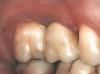

Second-stage surgery was performed after 4 months (Figure 8); healing abutments were placed and the soft tissue was allowed to heal for 5 more weeks. Then, splinted porcelain-fused-metal (PFM) crowns supported by custom gold abutments were delivered (Figure 9 and Figure 10).

Figure 8 At 4 months after treatment, the radiograph revealed the presence of a bone layer surrounding the implant.